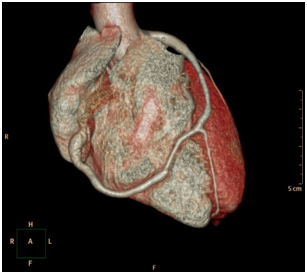

There was an arterio-venous fistula, arising from the distal LAD with an unclear drainage end into the right heart chambers (Figure 3) (Figure 4). There was a slow flow in the distal LAD beyond the fistula origin. Her LAD was type III, wrapping around the left ventricular apex, supplying the apical two-thirds of infero-posterior wall. The right coronary artery (RCA) was rudimentary and the left circumflex artery (LCx) was normal. To further study these abnormalities, she was scheduled for CT Coronary Angiogram which revealed a fistula arising from the distal LAD and courses anteriorly on the right ventricle measuring 3.3 mm just after its origin from the LAD, terminating into the superior aspect of the right ventricle (RV). The terminal part of the AV measures 11.8 mm (Figure 5) (Figure 6). The rest of the coronary findings were matching those seen in the conventional coronary angiography.

Figure 5 CT coronary angiogram: 3-dimentional picture showing the course of the CAVF across the right ventricle.